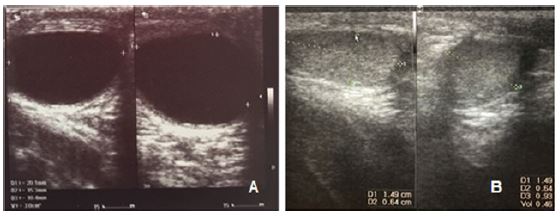

El caso corresponde a un lactante de 9 meses sin antecedentes clínicos, llevado a consulta por primera vez por presentar una masa testicular de 7 meses de evolución, debido al aumento progresivo del tamaño. En el examen físico se encontró una lesión circunscrita en el testículo derecho, de bordes bien definidos, de aproximadamente 1 cm de diámetro, no dolorosa, sin cambios inflamatorios locales. La ecografía evidenció un quiste simple intraparenquimatoso ( figura 1a). Los marcadores tumorales fueron negativos.

Ante los hallazgos clínicos, paraclínicos y ecográficos altamente sugestivos de quiste simple sintomático, se decidió llevar a exploración testicular por vía escrotal. Se identificó un gran quiste epidérmico que ocupaba el 70% del volumen testicular, el cual se enucleó en su totalidad respetando el parénquima residual ( figura 2). No se documentaron complicaciones perioperatorias. El estudio microscópico de la pieza evidenció un quiste con pared conformada por tejido fibroconjuntivo denso y tapizado por epitelio escamoso estratificado delgado, con queratinización superficial, sin evidencia de otros elementos teratogénicos o neoplásicos, compatible con un quiste epidermoide testicular.

Presentó adecuada evolución postoperatoria, sin dolor ni cambios tróficos testiculares, con adecuada cicatrización de la herida. Durante el seguimiento a tres años, no se documentó recidiva. La ecografía de control mostró un adecuado volumen testicular (volumen residual del testículo derecho de 0,64 ml), sin evidencia de lesiones intraparenquimatosas ( figura 1b).

La apariencia ecográfica varía dependiendo del grado de madurez, tamaño y compactación de la queratina que contiene, pues se han encontrado lesiones quísticas hasta sólidas, lo que hace difícil su diferenciación con tumores malignos ( 10). De acuerdo con Taghavi y Hutson ( 25), los hallazgos de ultrasonido permiten clasificar el quiste epidermoide en uno de cuatro grupos: apariencia en anillo de cebolla (tipo I), masa hiperecoica con sombra acústica posterior (tipo II), masa hipoecoica con reborde bien definido (tipo III) ( figura 1a) y lesión heterogénea con márgenes mal definidos y pequeños focos de calcificación (tipo IV) ( 26).